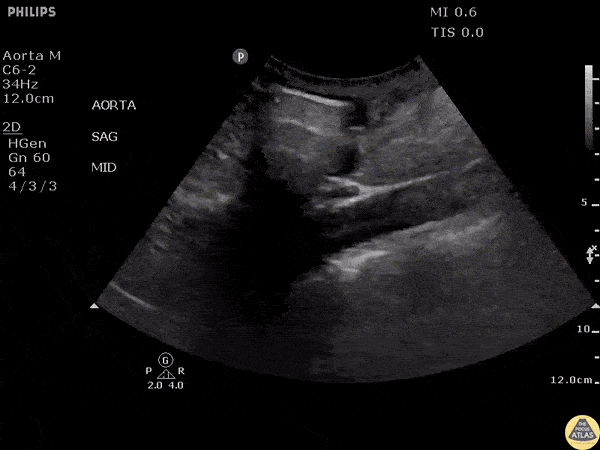

Aorta - Aortic Dissection

Patient presented with symptoms of stroke. Echo revealed pericardial effusion and aortic US showed a dissection flap emphasizing the importance of POCUS prior to TPA. Image courtesy of Robert Jones DO, FACEP @RJonesSonoEM Director, Emergency Ultrasound; MetroHealth Medical Center; Professor, Case Western Reserve Medical School, Cleveland, OH View his original post here